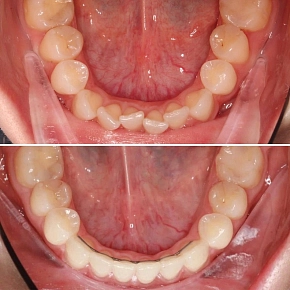

Успешное ортодонтическое лечение